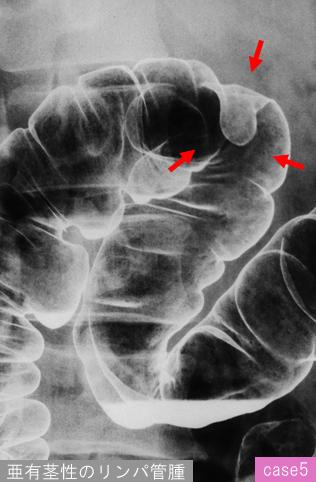

질환(병리주체)의 분류 기타/

부위(장기별) 대장/횡행

검사방법 X-P

종양의 최대경(밀리미터) 20~24